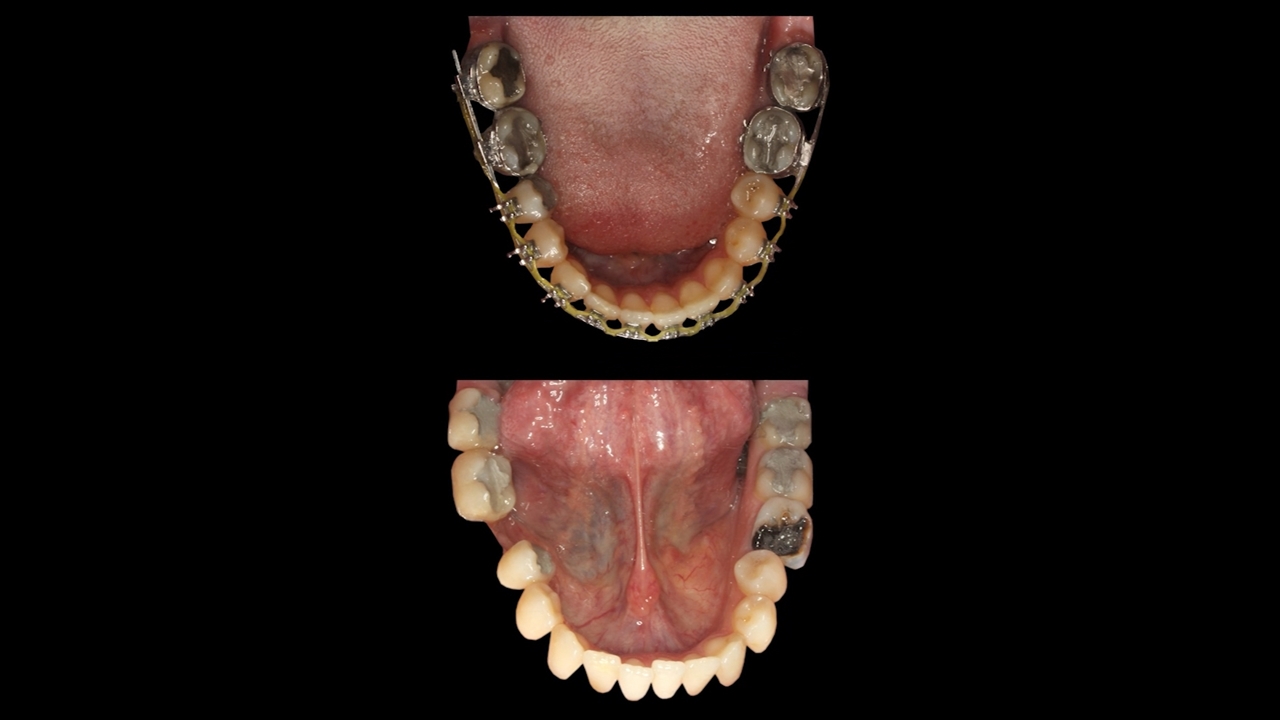

از دست دادن دندان یک اتفاق طبیعی است، گاه در اثر ضربه یا یک بیماری ممکن است اتفاق بیفتد. با ارتودنسی می‌توان به جای استفاده از ایمپلنت و یا روش‌های درمانی دیگر جای خالی دندان را پر کرد. در این کیس با ارتودنسی دندان ناحیه 6 پایین که به شدت تخریب شده بود پر شد.